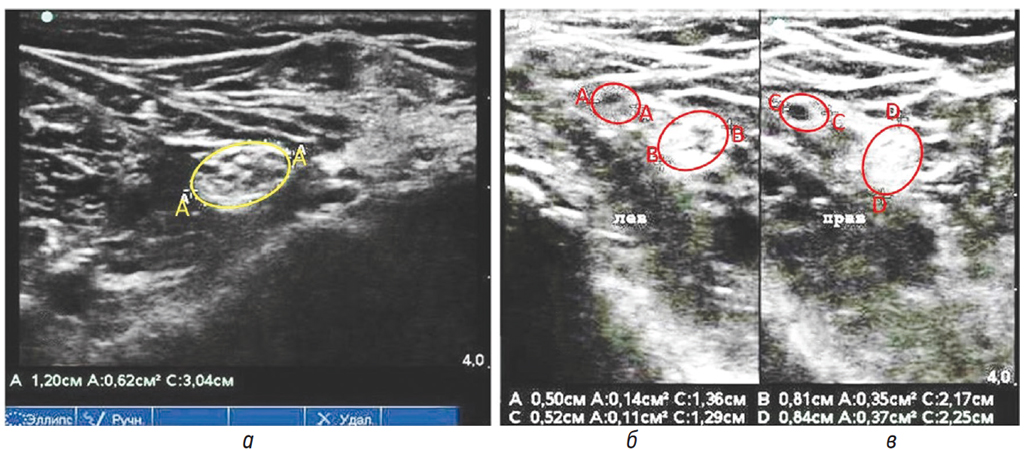

По данным УЗИ нервов верхних и нижних конечностей от декабря 2019 г.: ППС седалищного нерва на уровне нижней трети бедра: слева от 62 до 68 мм2, справа от 42 до 62 мм2. Норма: 42,4 + 13,2 мм2 [11]. Малоберцовый нерв неравномерной толщины, с наибольшим утолщением на уровне подколенной ямки, гипоэхогенный с увеличением отдельных фасцикул. Признаки сдавления на уровне малоберцового канала не определяются. ППС на уровне подколенной ямки: слева от 9 до 16 мм2, справа от 9 до 11 мм2. Норма [11]: 8,54 + 2,89 мм2. Большеберцовый нерв — неравномерной толщины, с наибольшим утолщением на уровне подколенной ямки и медиальной лодыжки, гиперэхогенный с увеличением отдельных гипоэхогенных фасцикул (больше слева). Признаки сдавления не определяются. ППС: слева от 35 до 43 мм2, справа от 37 до 43 мм2. Норма [11]: 23,7 + 5,7 мм2 (рис. 4).

Рис. 4. Сонограмма левого седалищного нерва на уровне нижней трети бедра (а); сонограмма левого малоберцового и большеберцового нервов на уровне подколенной ямки (б); сонограмма правого малоберцового и большеберцового нервов на уровне подколенной ямки (в). Примечание: а) — ППС левого седалищного нерва (эллипс АА); б) — ППС левого малоберцового нерва (эллипс АА), ППС левого большеберцового нерва (эллипс ВВ); в) — ППС правого малоберцового нерва (эллипс СС); ППС правого большеберцового нерва (эллипс DD)